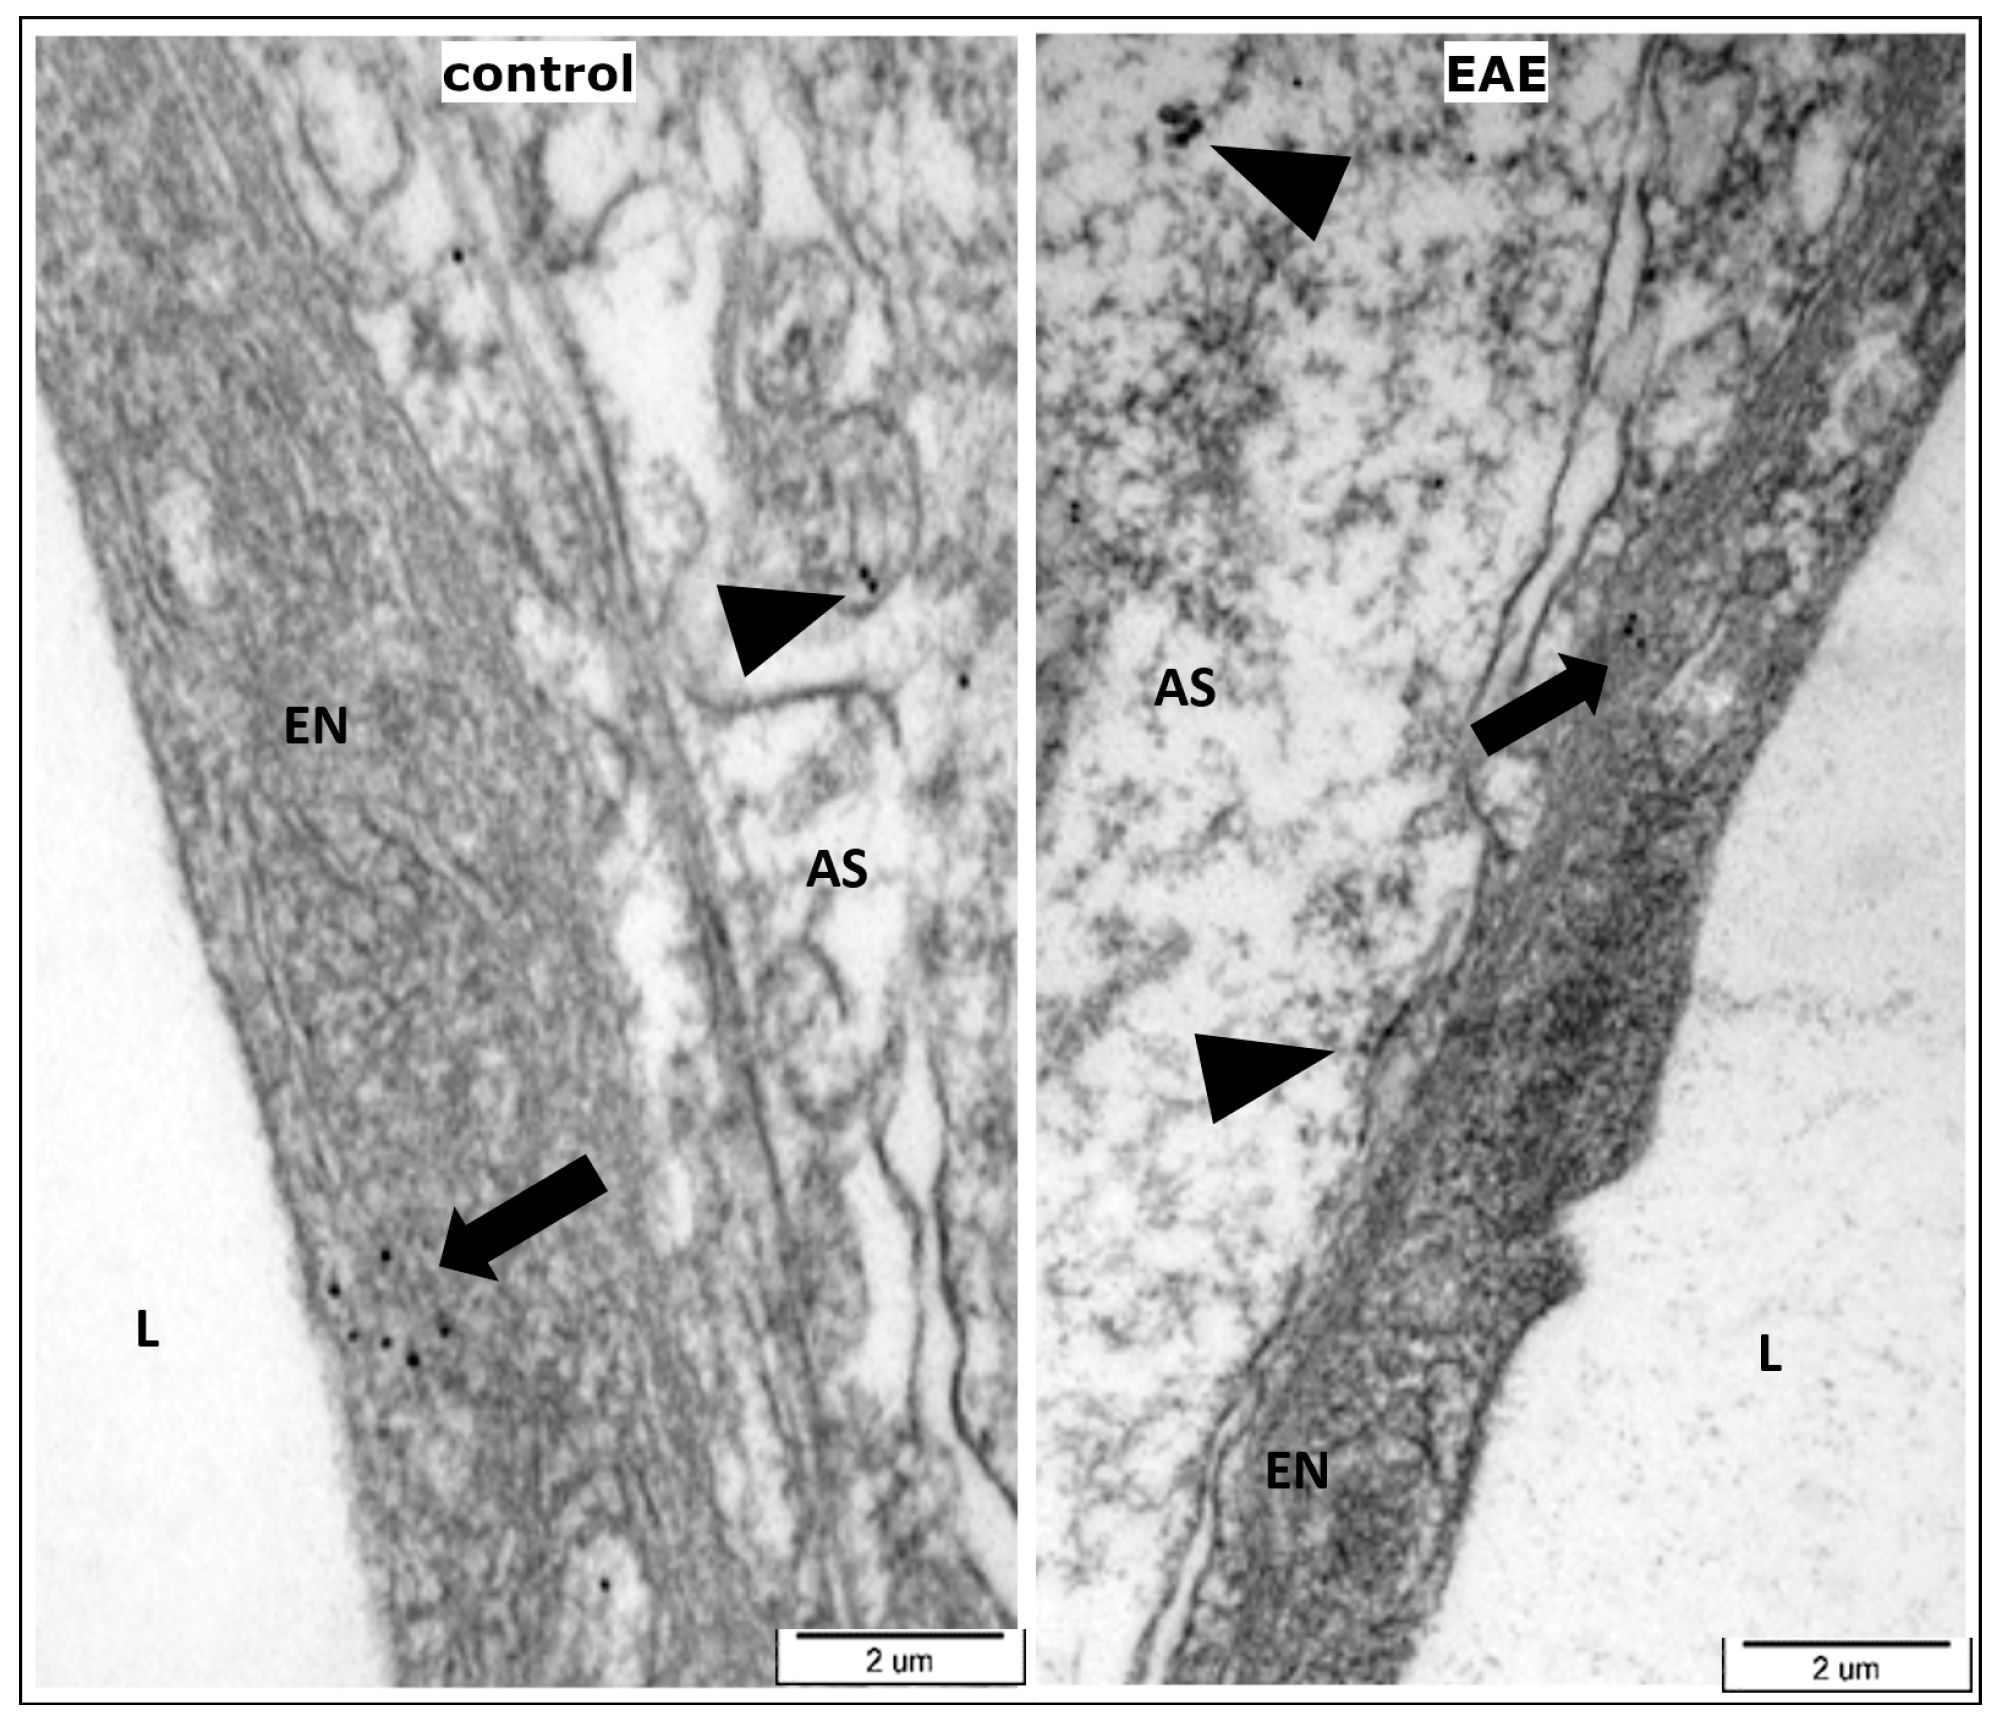

3.2. The BBB Integrity during the Course of EAE–Functional Test and TEM Analysis

- Dabrowska-Bouta, B.; Sulkowski, G.; Frontczak-Baniewicz, M.; Skalska, J.; Salek, M.; Orzelska-Gorka, J.; Struzynska, L. Ultrastructural and Biochemical Features of Cerebral Microvessels of Adult Rat Subjected to a Low Dose of Silver Nanoparticles. Toxicology 2018, 408, 31–38. [Google Scholar] [CrossRef]

- Roy, S.; Sarkar, C. Ultrastructural Study of Micro-Blood Vessels in Human Brain Tumors and Peritumoral Tissue. J. Neuro-Oncol. 1989, 7, 283–294. [Google Scholar] [CrossRef]